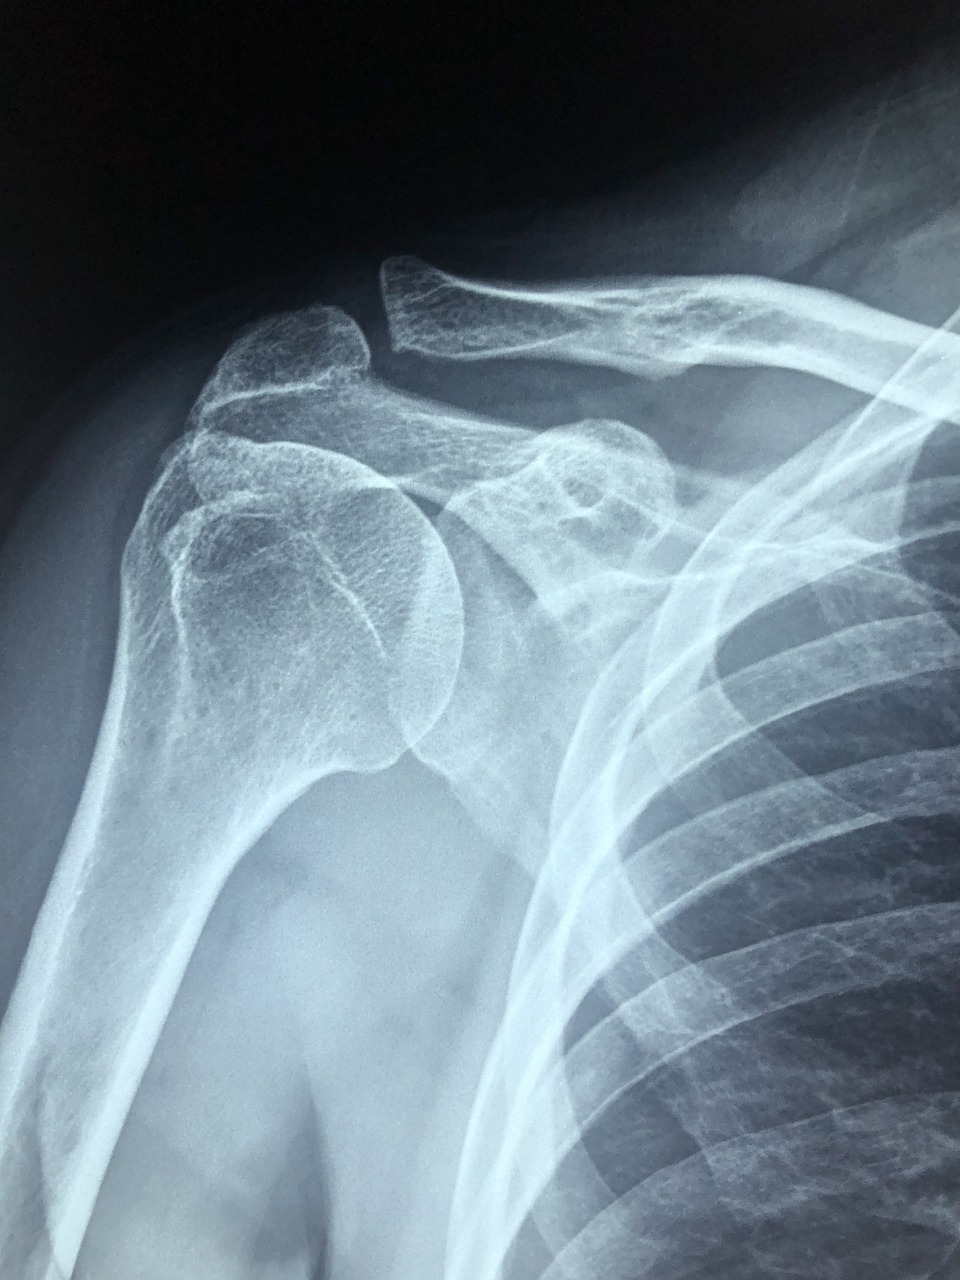

특히 회전근개파열이나 석회성건염 등 만성 어깨 질환에 효과가 있다는 말이 퍼지면서 체외충격파 치료 비용이나 횟수, 그리고 보험 적용 여부까지 궁금해하는 분들이 늘고 있는데요.

체외충격파 치료(ESWT)는 몸 바깥에서 충격파를 주어, 손상된 조직을 자극하고 자가 회복을 유도하는 방식의 비수술 치료법입니다. 주로 근골격계 질환에 적용되며, 시술 시간은 약 10~15분 정도로 짧고 마취나 입원이 필요 없다는 장점이 있습니다.

특히 어깨 회전근개파열 초기나 석회성 건염, 오십견 등 만성 염증성 질환에 많이 사용되며, 일상생활에 큰 부담 없이 통증 개선 효과를 볼 수 있어 최근 더욱 주목받고 있어요.

보통은 초음파나 MRI 등으로 병변의 위치를 확인한 후 치료에 들어가며, 근육의 혈류 개선과 세포 재생을 촉진해 통증 완화뿐 아니라 운동 범위 회복에도 도움을 줍니다.